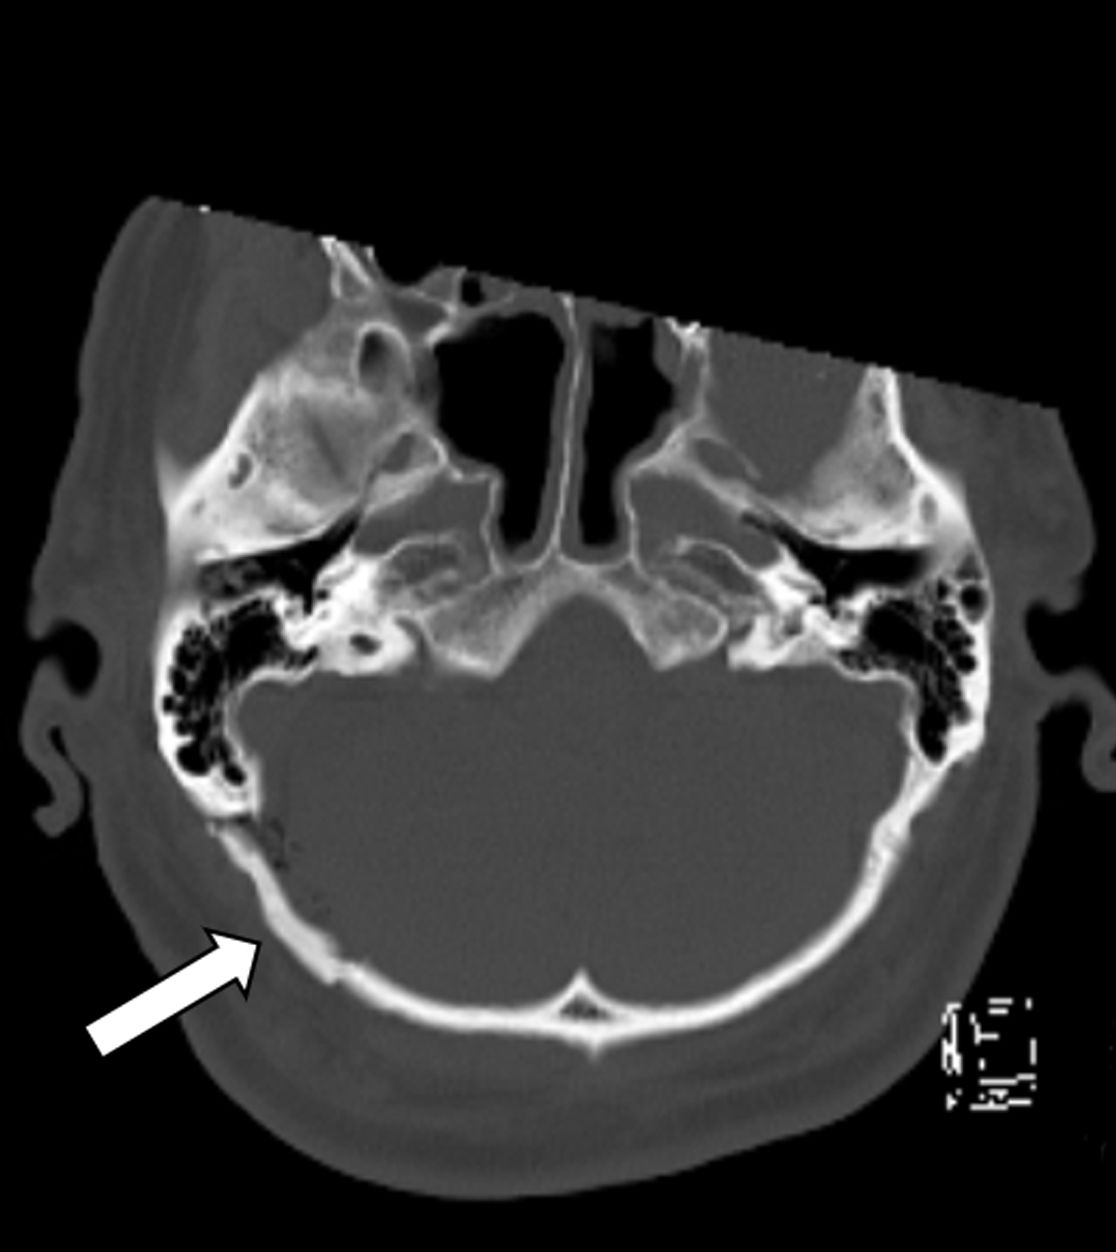

Status nach mikrovaskulärer Dekompression über einen Zugang hinter dem Ohr (Pfeil)